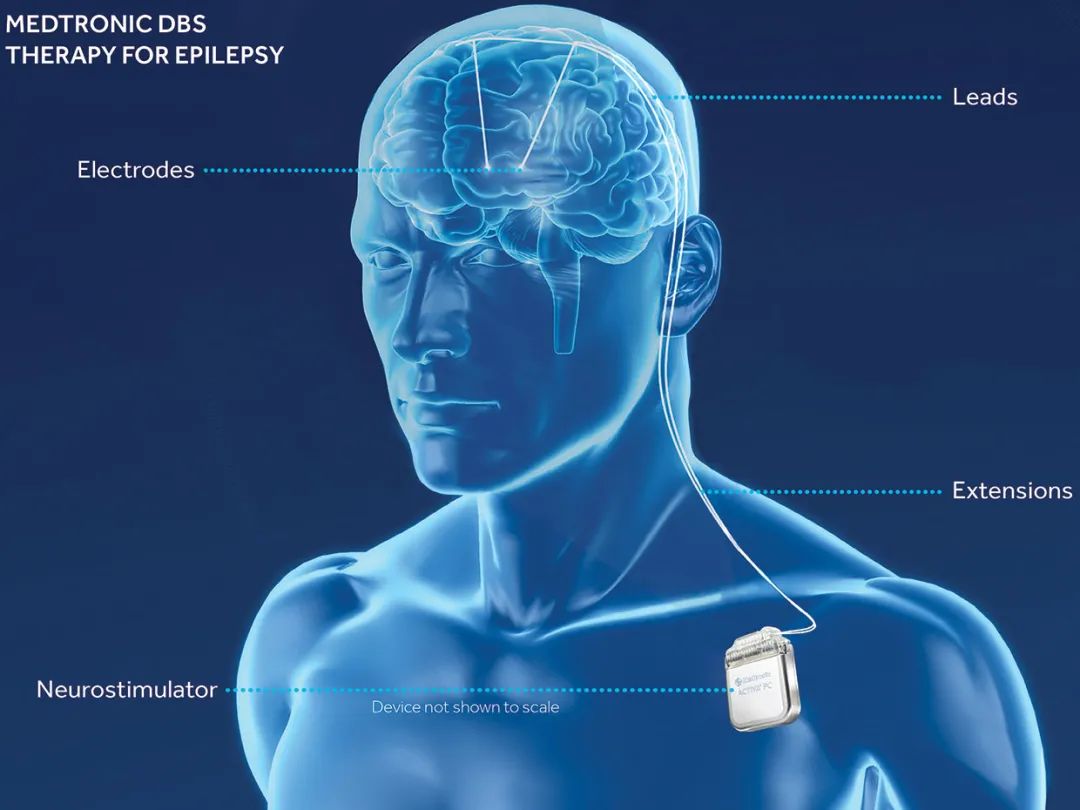

神经植入最成熟的临床应用之一是脑深部电刺激(DBS)疗法。在这种疗法中,通过外科手术将电极植入大脑深处,用电刺激特定结构,以减少各种脑部疾病的症状。

Illustration: Reprinted with the permissionof Medtronic

Medtronic的DBS系统目前常用来治疗帕金森病的运动症状。

1997年,美国食品药品监督管理局(FDA)首次批准使用DBS治疗原发性震颤。此后,FDA或其他全球监管机构批准DBS治疗帕金森病、肌张力障碍、耳鸣、癫痫、强迫症和神经性疼痛。DBS还被研究用于治疗图雷特综合症和抑郁症等精神疾病。据估计,全球有超过150,000 人接受了 DBS 植入。